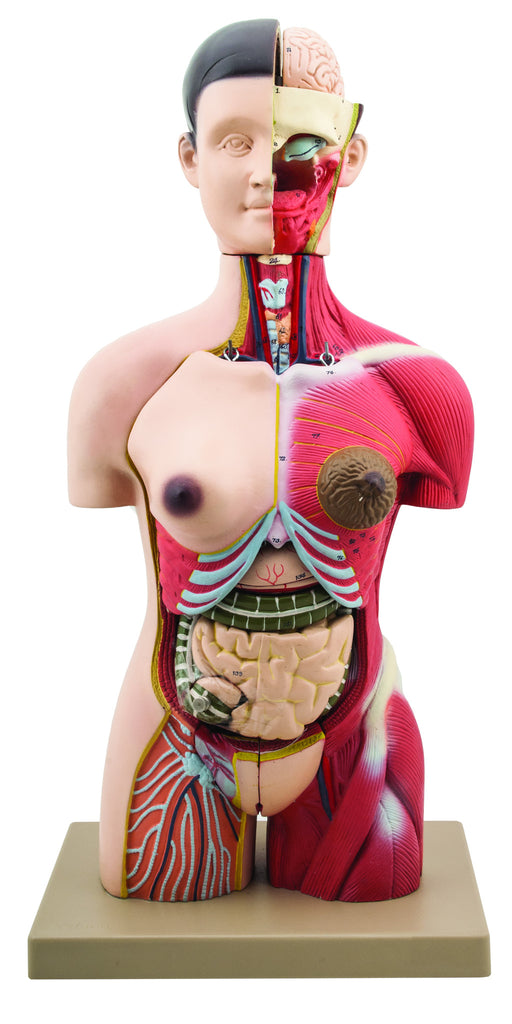

Half Muscle Torso with Dual Sex Organs 28 Parts

The detailed, life size 3D rendering of the human torso with its vibrantly colored anatomy is ideal for studying the structure and function of th...

View full detailsAM16004 -